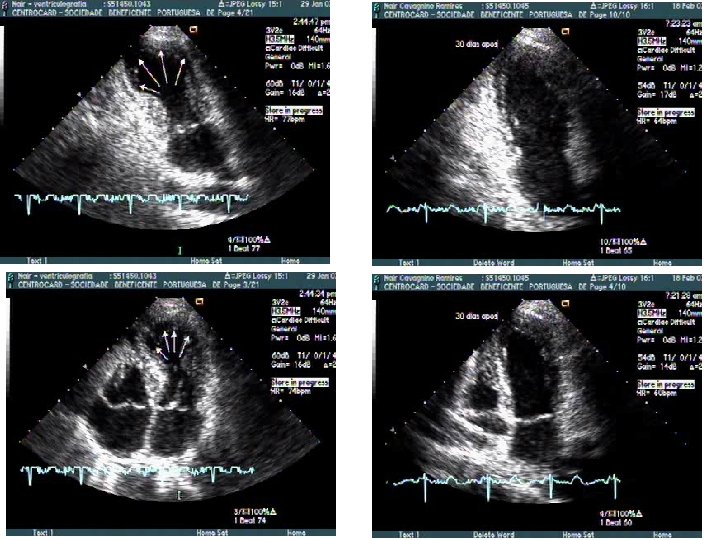

Repouso 4 c diástole Dipiridamol 4 c 2 c diástole 4 c sístole 2 c sístole

r e p o u s o 4 c diastole 2 c diastole 4 c sístole 2 c sístole D I P t o t al antes cirurgia 30 dias cirurgia 4 c diastole 2 c sístole